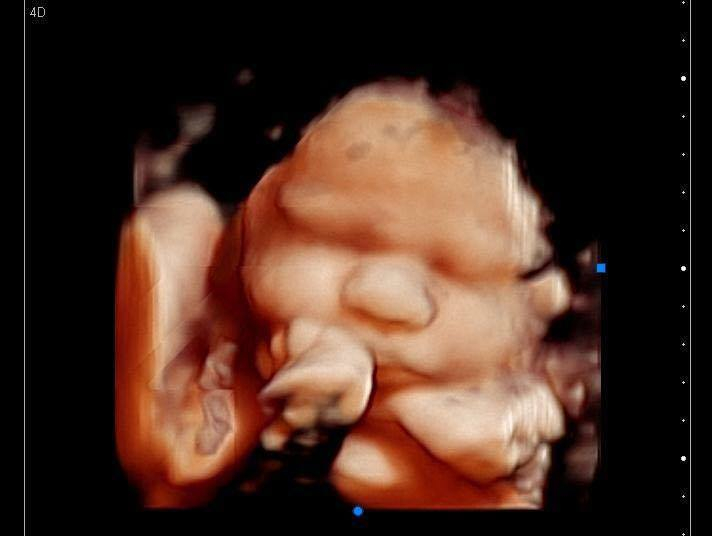

3d Ultrasound Edmond Ok

Home Anticipation Ultrasound Studio